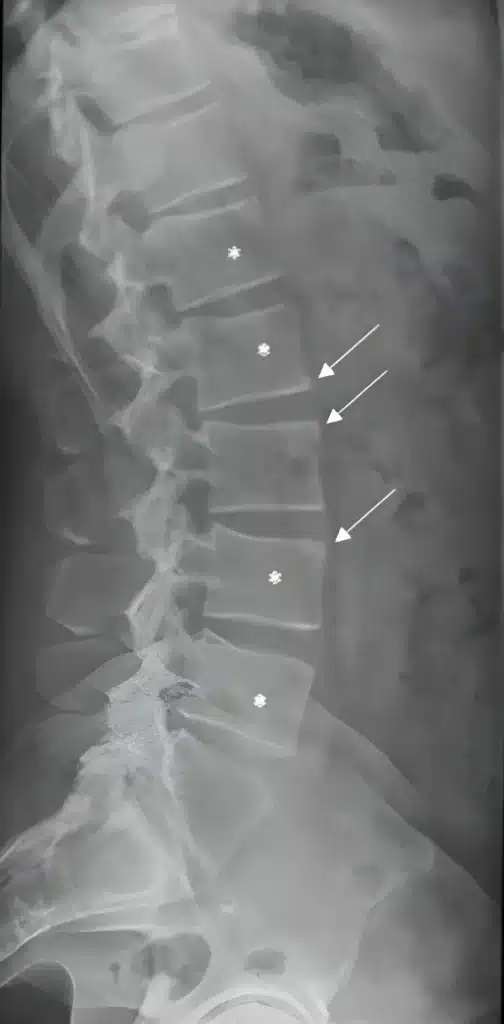

Une spondylarthrite ou spondyloarthrite axiale est un rhumatisme inflammatoire chronique qui affecte des parties de la colonne vertébrale et du bassin telles que les os, les muscles et les ligaments. Les premiers symptômes des SpA axiales surviennent dans la très grande majorité des cas entre 20 et 30 ans. Une spondylarthrite peut évoluer sur des années et atteindre plusieurs articulations. Si l’axSpA n’est pas traitée, des formations osseuses peuvent se développer, provoquant la fusion de la colonne vertébrale.

Dans leur étude révolutionnaire publiée dans le Journal of Clinical Investigation, les recherches menées par l’équipe de Lories et Luyten ont révélé les mécanismes moléculaires complexes qui sous-tendent le processus de formation osseuse dans la spondyloarthrite axiale. Grâce à une expérimentation minutieuse et à une analyse approfondie, ils ont mis au jour un réseau complexe d’interactions cellulaires et de voies de signalisation qui contribuent à la formation de nouveaux tissus osseux. Ce travail de pionnier a fourni des informations sans précédent sur les processus biologiques fondamentaux impliqués, ouvrant la voie au développement d’interventions thérapeutiques ciblées.

Une autre étude de référence, signée par Lories et Luyten et publiée dans Arthritis and Rheumatology, a révélé une chose intrigante: l’inflammation et la néoformation osseuse, bien que intrinsèquement liées dans la spondylarthrite, sont régies par des processus moléculaires distincts. Cette découverte a transformé la compréhension de la maladie par la communauté scientifique, en démontrant que l’inflammation et la néoformation osseuse ne sont pas simplement corrélées, mais plutôt des entités indépendantes. Cette découverte cruciale a le potentiel de remodeler les stratégies de traitement employées par les professionnels de la santé, en leur permettant d’aborder ces aspects individuellement et d’adapter les thérapies aux besoins uniques de chaque patient.